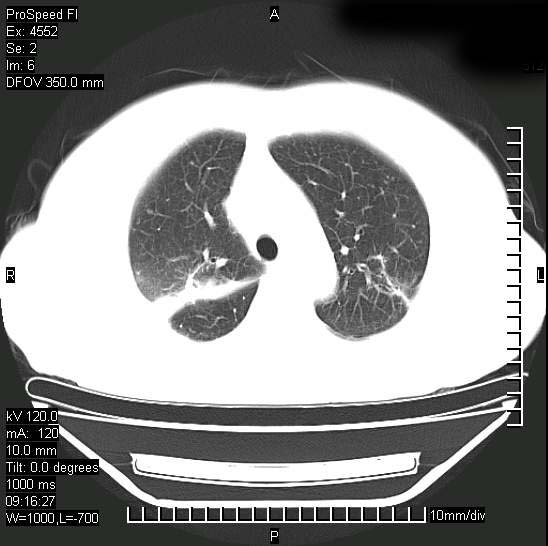

十几年前曾患肺结核,一周前突咳血约100ml,中性粒细胞稍高,诊断两上肺陈旧结核,下肺炎症,给予抗炎治疗,近几日晚上高热,39度,仍咳少量血,4天前ct及今天ct上传。

[face=黑体]8月30日[/face]

今天ct

支持陈旧性肺结核并两下肺感染,两侧胸腔积液。

短短几天内,病变范围明显增多扩大,以左侧明显,而且双侧出现胸水,还是考虑感染.

支持  结核ban感染,节段性肺不张,支气管内膜结核可能

短短几天内,病变范围明显增多扩大,以左侧明显,而且双侧出现胸水,我更多考虑左侧中心性肺癌并并阻塞性不张及肺炎,炎症变化也太快了!

无论是肿瘤还是炎症4天的时间都发展够快的,并且还在治疗中,如果说是左肺癌那么右肺的病变不好解释,本人更加倾向于炎症,左肺舌叶支气管被痰栓或血凝块堵塞,造成阻塞性肺炎。

1)两肺结核并感染。2)不排除左肺上叶中央型肺癌并阻塞性肺炎、肺不张可能;建议行纤支镜检查。3)右肺门及纵隔淋巴结肿大。4)双侧胸腔积液。

陈旧性肺结核及左下肺不张,咯血后肺部感染,双胸腔积液,高热可能与痰液引流不畅有关。